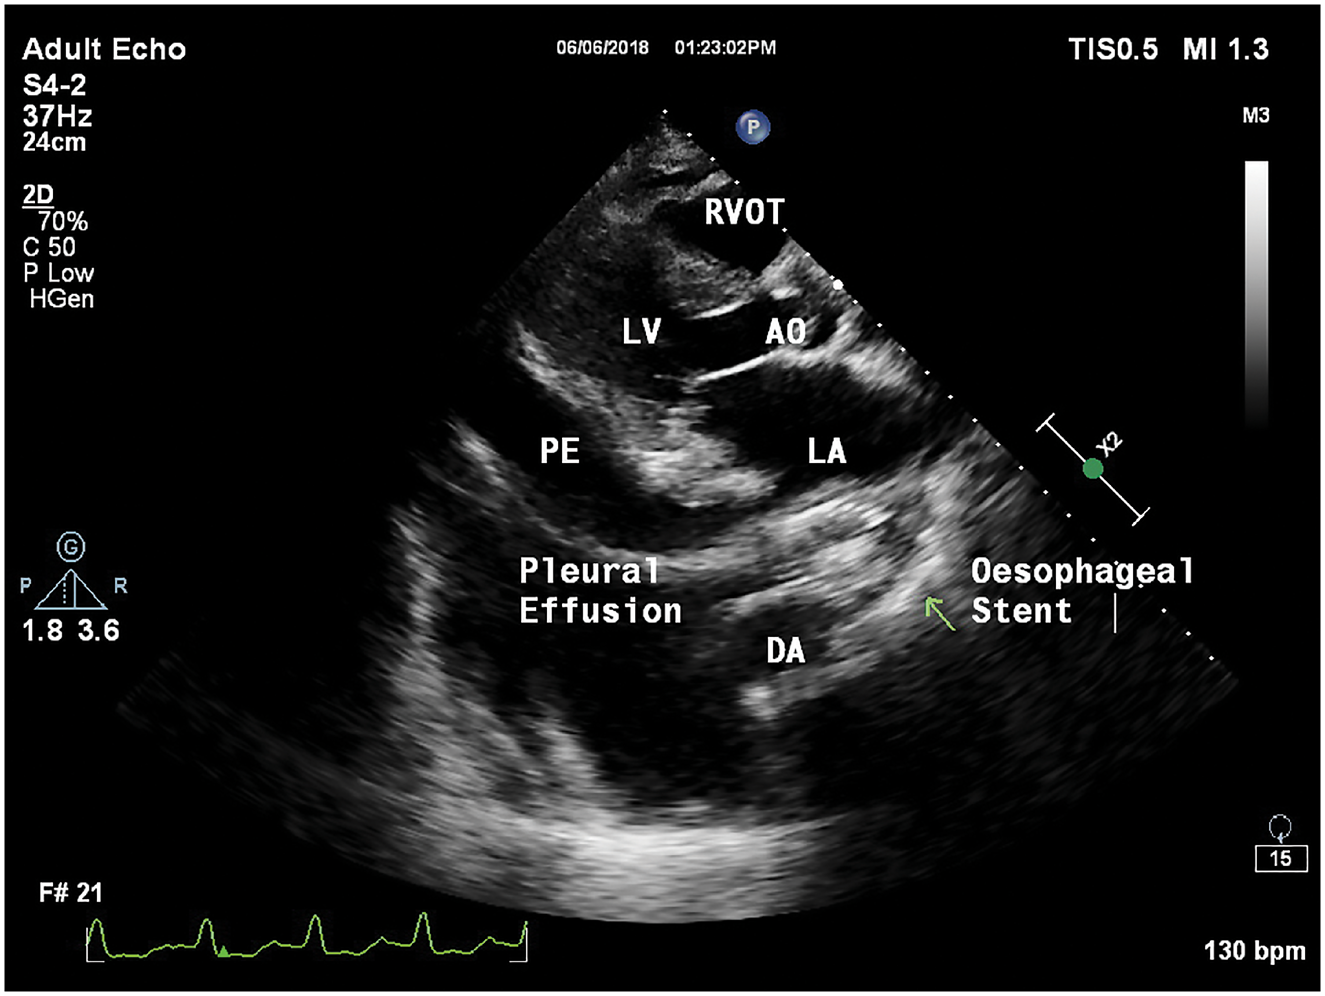

经胸超声心动图检查显示,左心房后有金属阴影,即食管支架(图2,图3)